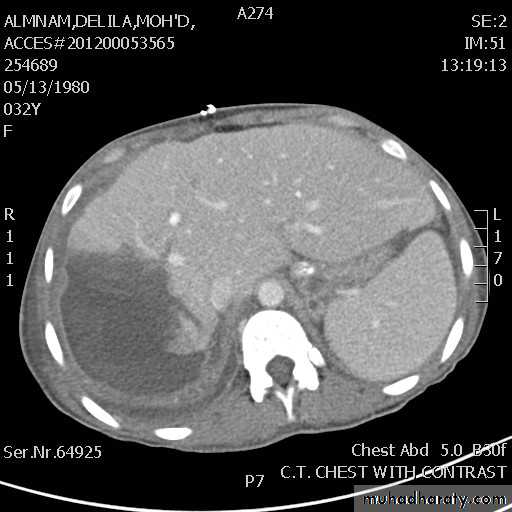

Malignant neoplasms:

hepatocellular carcinoma